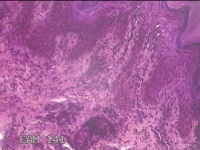

左侧足趾皮下结节

性别

女

年龄

32岁

临床诊断

皮下结节

一般病史

发现左侧足趾皮下结节2年余,无明显疼痛及不适。

标本名称

大体所见

灰白暗红色带皮肤肿物0.8x0.5x0.3cm一个,表面糜烂,切开结节呈实性,切面灰白暗红色,质中。